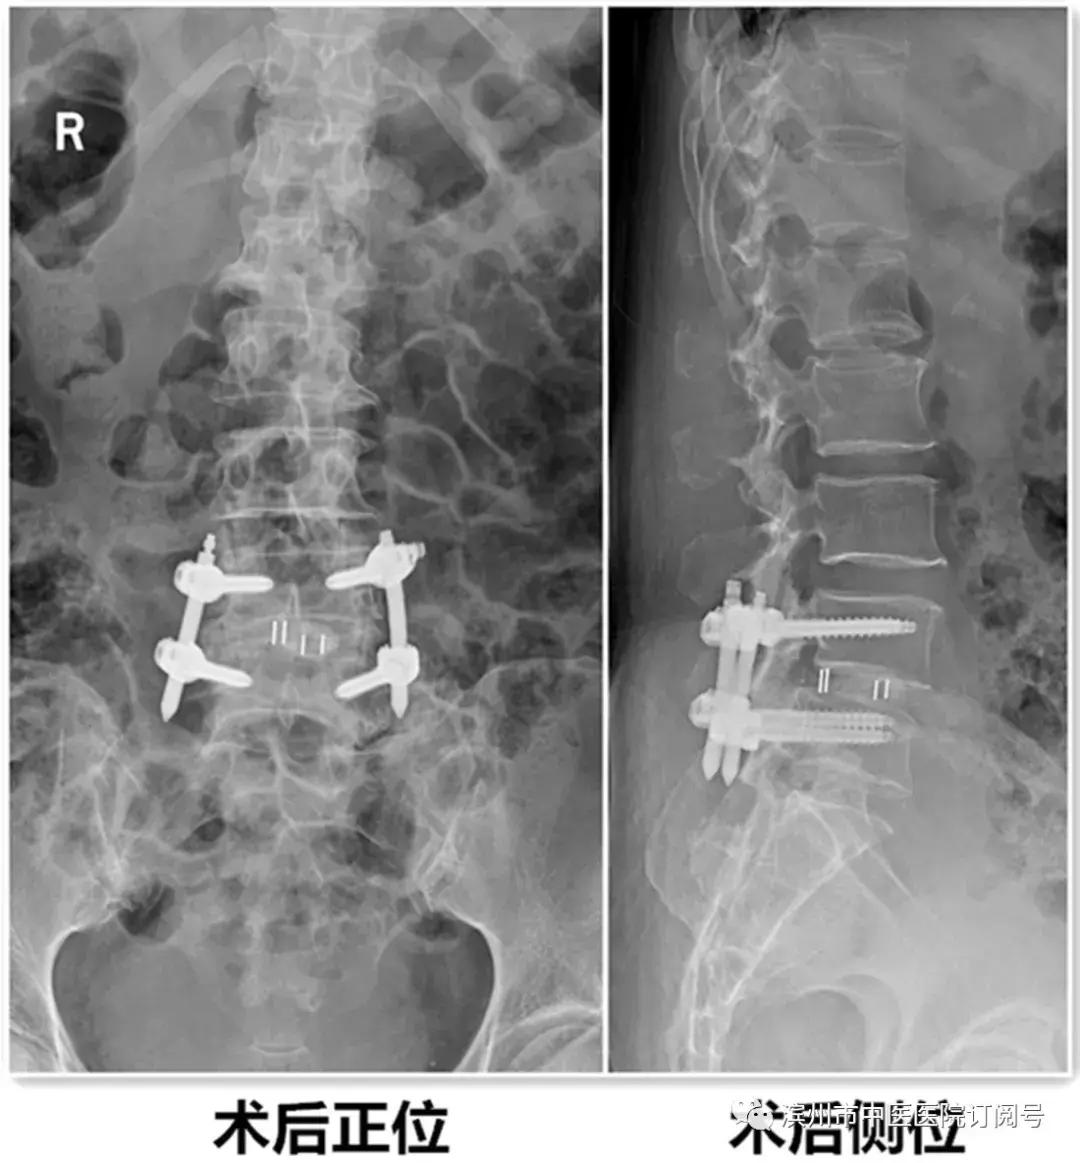

在使用国际领先水平的镜下处理工具及器械的同时,结合我院已有的天玑骨科手术机器人、神经电生理检测设备辅助下,我院安全、成功的完成了这台复杂手术。

患者术后第3天带支具下床活动,症状基本消失,并行X线检查。见滑脱复位,且椎间隙高度恢复。